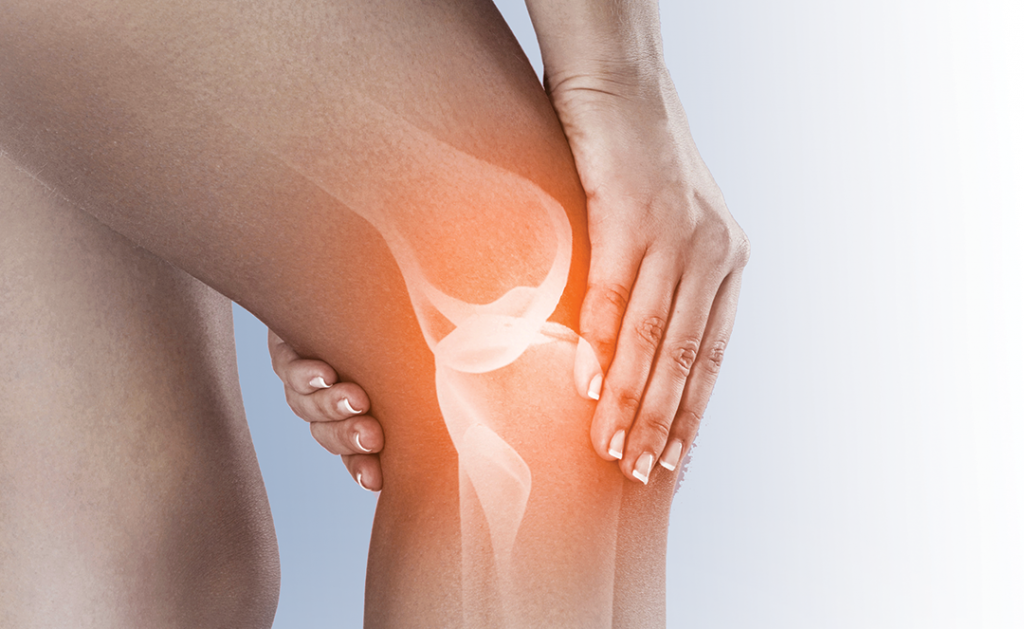

Acupuncture For Knee Pain

1. Acupuncture is best known for the management of pain and reducing inflammation 2. Osteoarthritis of knee ( OA Knee )is the most common cause of knee […]